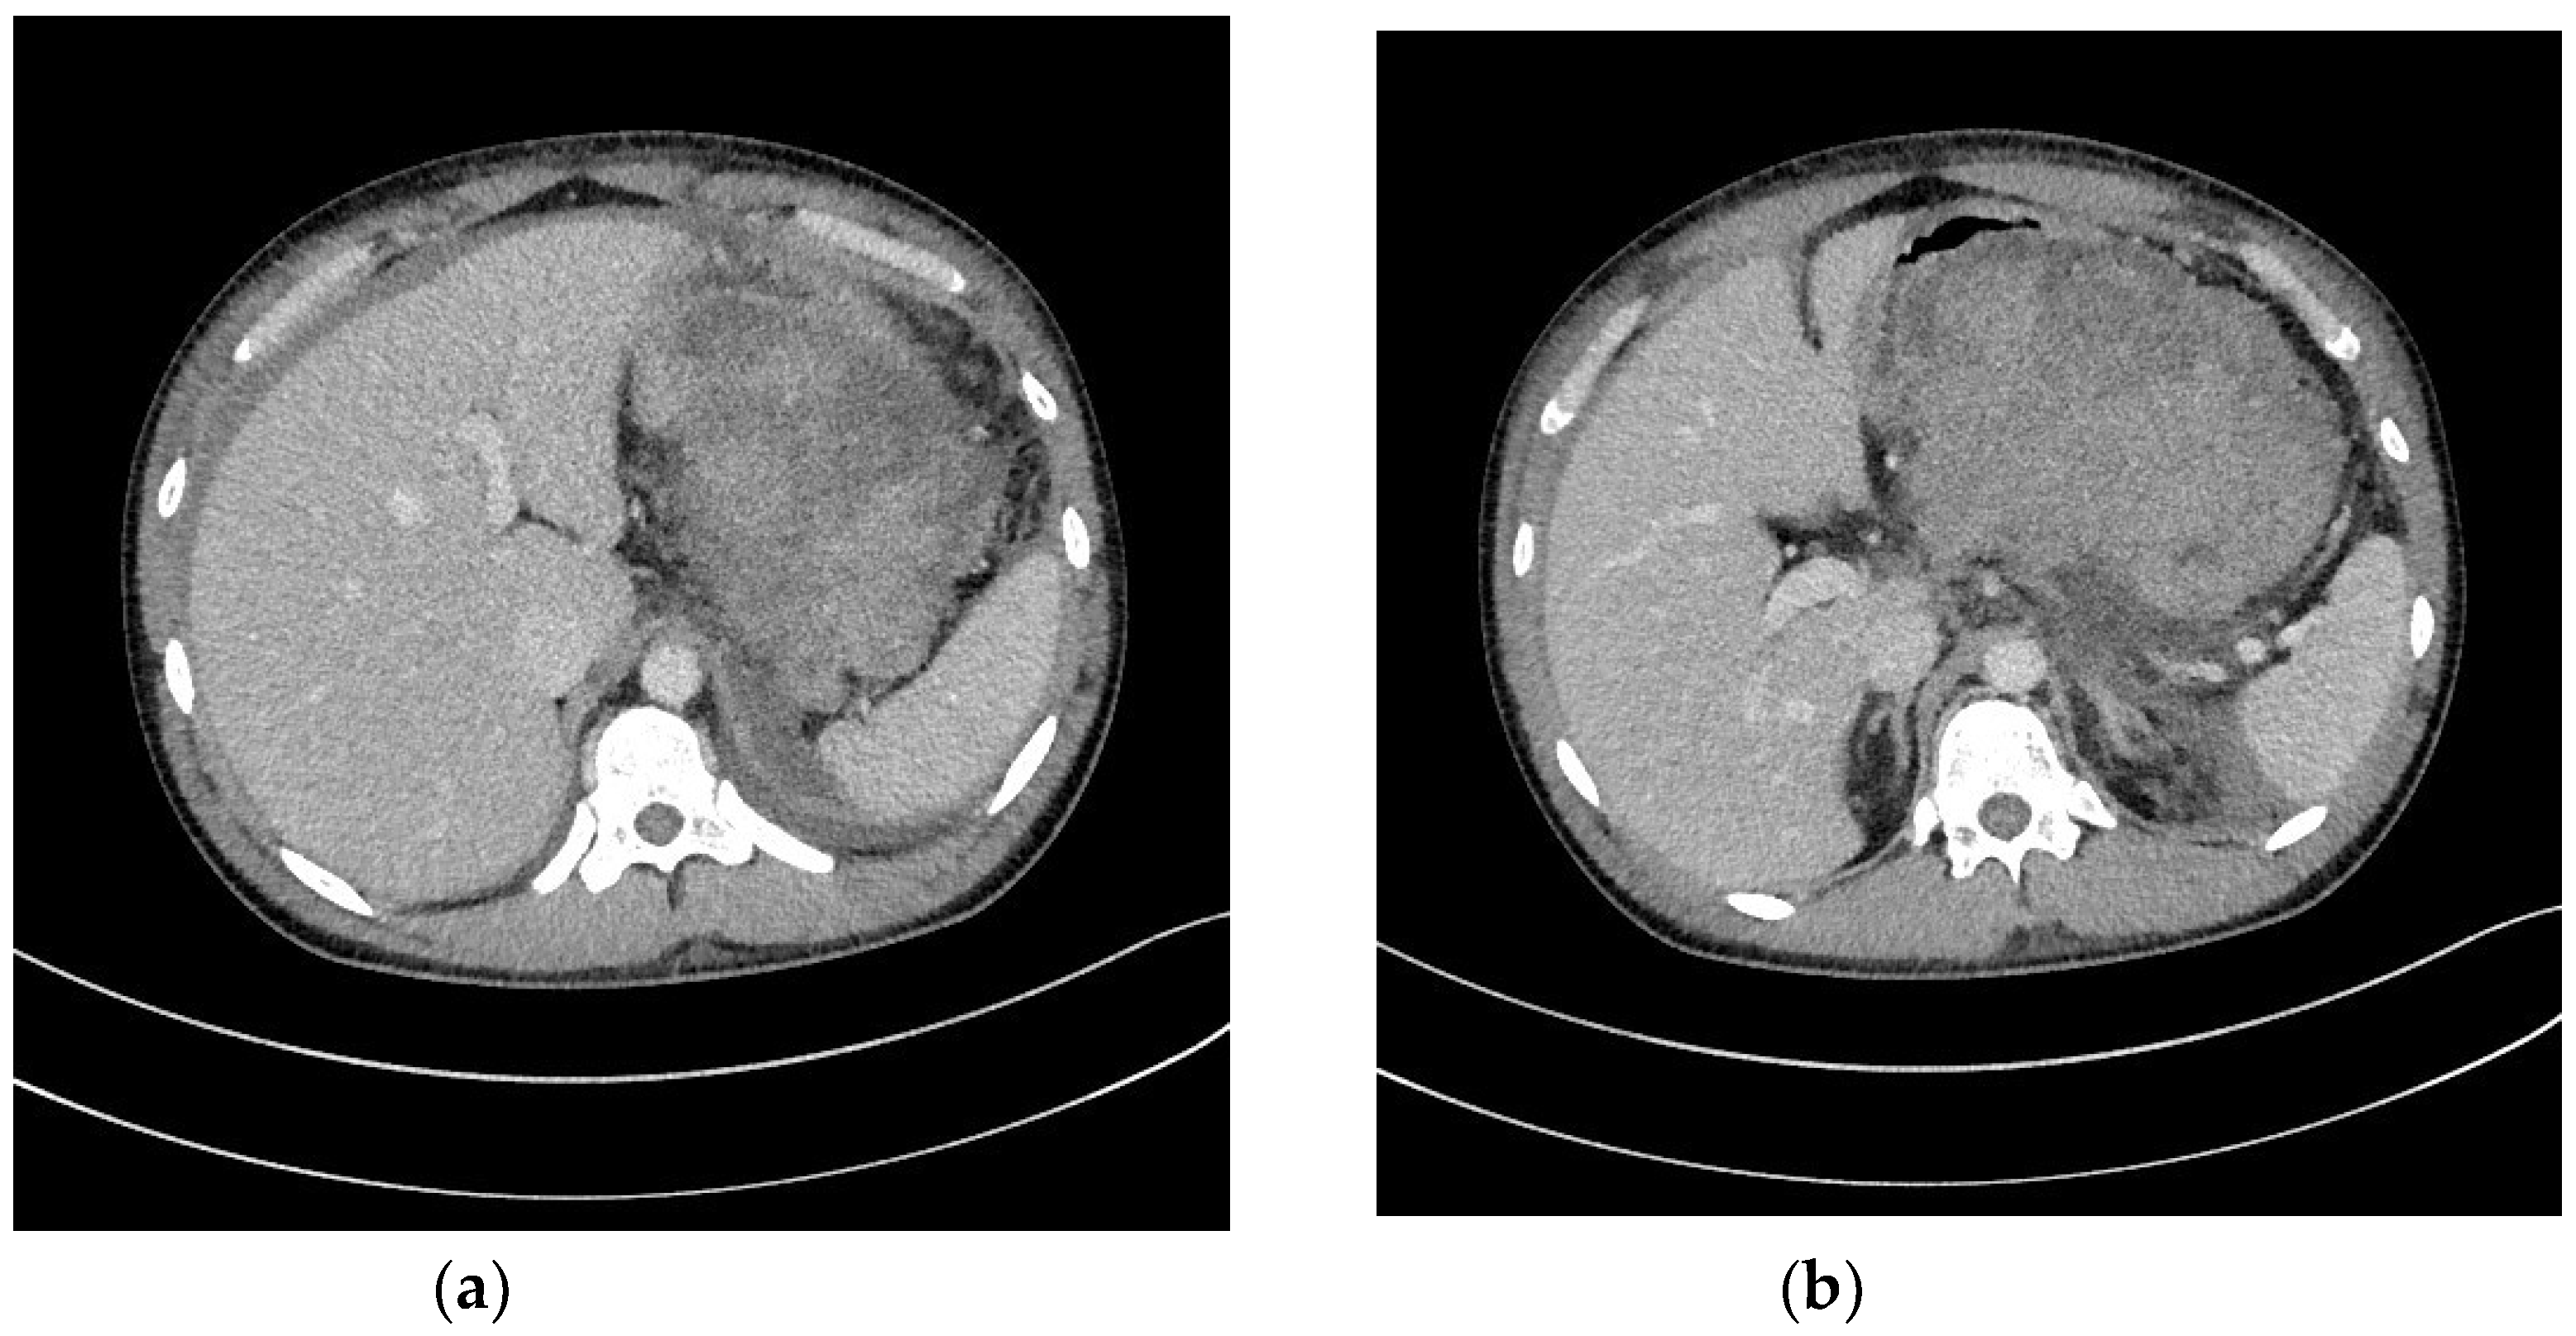

| Transmural endoscopic drainage with use of plastic stents | Active (with nasal drain) or passive (without nasal drain) transmural drainage enabled via insertion of plastic stent or stents through the transmural fistula into lumen of necrotic cavity. Mostly used in cases of well-liquefied collections of WOPN with small number of necrotic tissues in the lumen of WOPN, which usually take place after six weeks from the beginning of ANP. This type of drainage should be used in cases, where there is no necessity to perform endoscopic necrosectomy. |